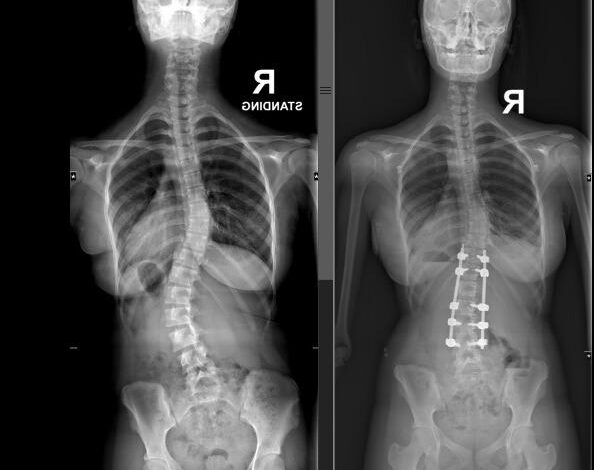

नई दिल्ली: नोएडा की एक होनहार कक्षा 10 की छात्रा 13 साल की आद्या ने जैसे ही अपने बोर्ड एग्ज़ाम खत्म किए, उसकी ज़िंदगी अचानक बदल गई। उसे एडोलेसेंट आइडियोपैथिक स्कोलियोसिस नाम की बीमारी हो गई। इस बीमारी में रीढ़ की हड्डी असामान्य तरीके से मुड़ जाती है। यह बीमारी उसके शरीर में स्थायी विकलांगता और आंतरिक समस्याएं पैदा कर सकती थी। लेकिन कुछ ही दिनों में आद्या ने अमृता हॉस्पिटल, फरीदाबाद में एक जटिल रीढ़ की सर्जरी करवाई। सर्जरी के बाद वह न सिर्फ शारीरिक रूप से ठीक हुई, बल्कि मानसिक रूप से भी और मजबूत महसूस करने लगी।

डॉ. तरुण सूरी ने बताया, “जब आद्या हमारे पास आई, तब उसकी रीढ़ की हड्डी लगभग 50 डिग्री तक मुड़ चुकी थी, इस हालत में सर्जरी करना बहुत जरूरी था। यह झुकाव सिर्फ दिखने की बात नहीं थी। अगर समय पर इलाज न होता, तो यह बच्ची के फेफड़ों और दिल की कार्यक्षमता को भी नुकसान पहुंचा सकता था। वह बोर्ड एग्ज़ाम की तैयारी कर रही थी और सामाजिक दबाव भी झेल रही थी, इसलिए हम जानते थे कि इसका भावनात्मक असर भी बहुत गहरा होगा। हमारी टीम का मकसद सिर्फ बेहतरीन इलाज देना नहीं था, बल्कि उसे पूरी तरह शारीरिक और मानसिक रूप से ठीक करना भी था। हम इसमें कामयाब हुए और उसे एक स्वस्थ जीवन जीने में मदद कर पाए।”

हर 10 में से 1 बच्चे को स्कोलियोसिस होता है, फिर भी यह बीमारी अक्सर समय पर पहचानी नहीं जाती। यह सबसे ज्यादा 10 से 15 साल की उम्र के बच्चों में पाई जाती है। लड़कियों में यह समस्या लड़कों की तुलना में 7 गुना ज्यादा होती है। गंभीर केसों में खासकर जब रीढ़ की हड्डी 40 डिग्री से ज्यादा मुड़ जाती है, तो सर्जरी करवाने की जरूरत पड़ती है।